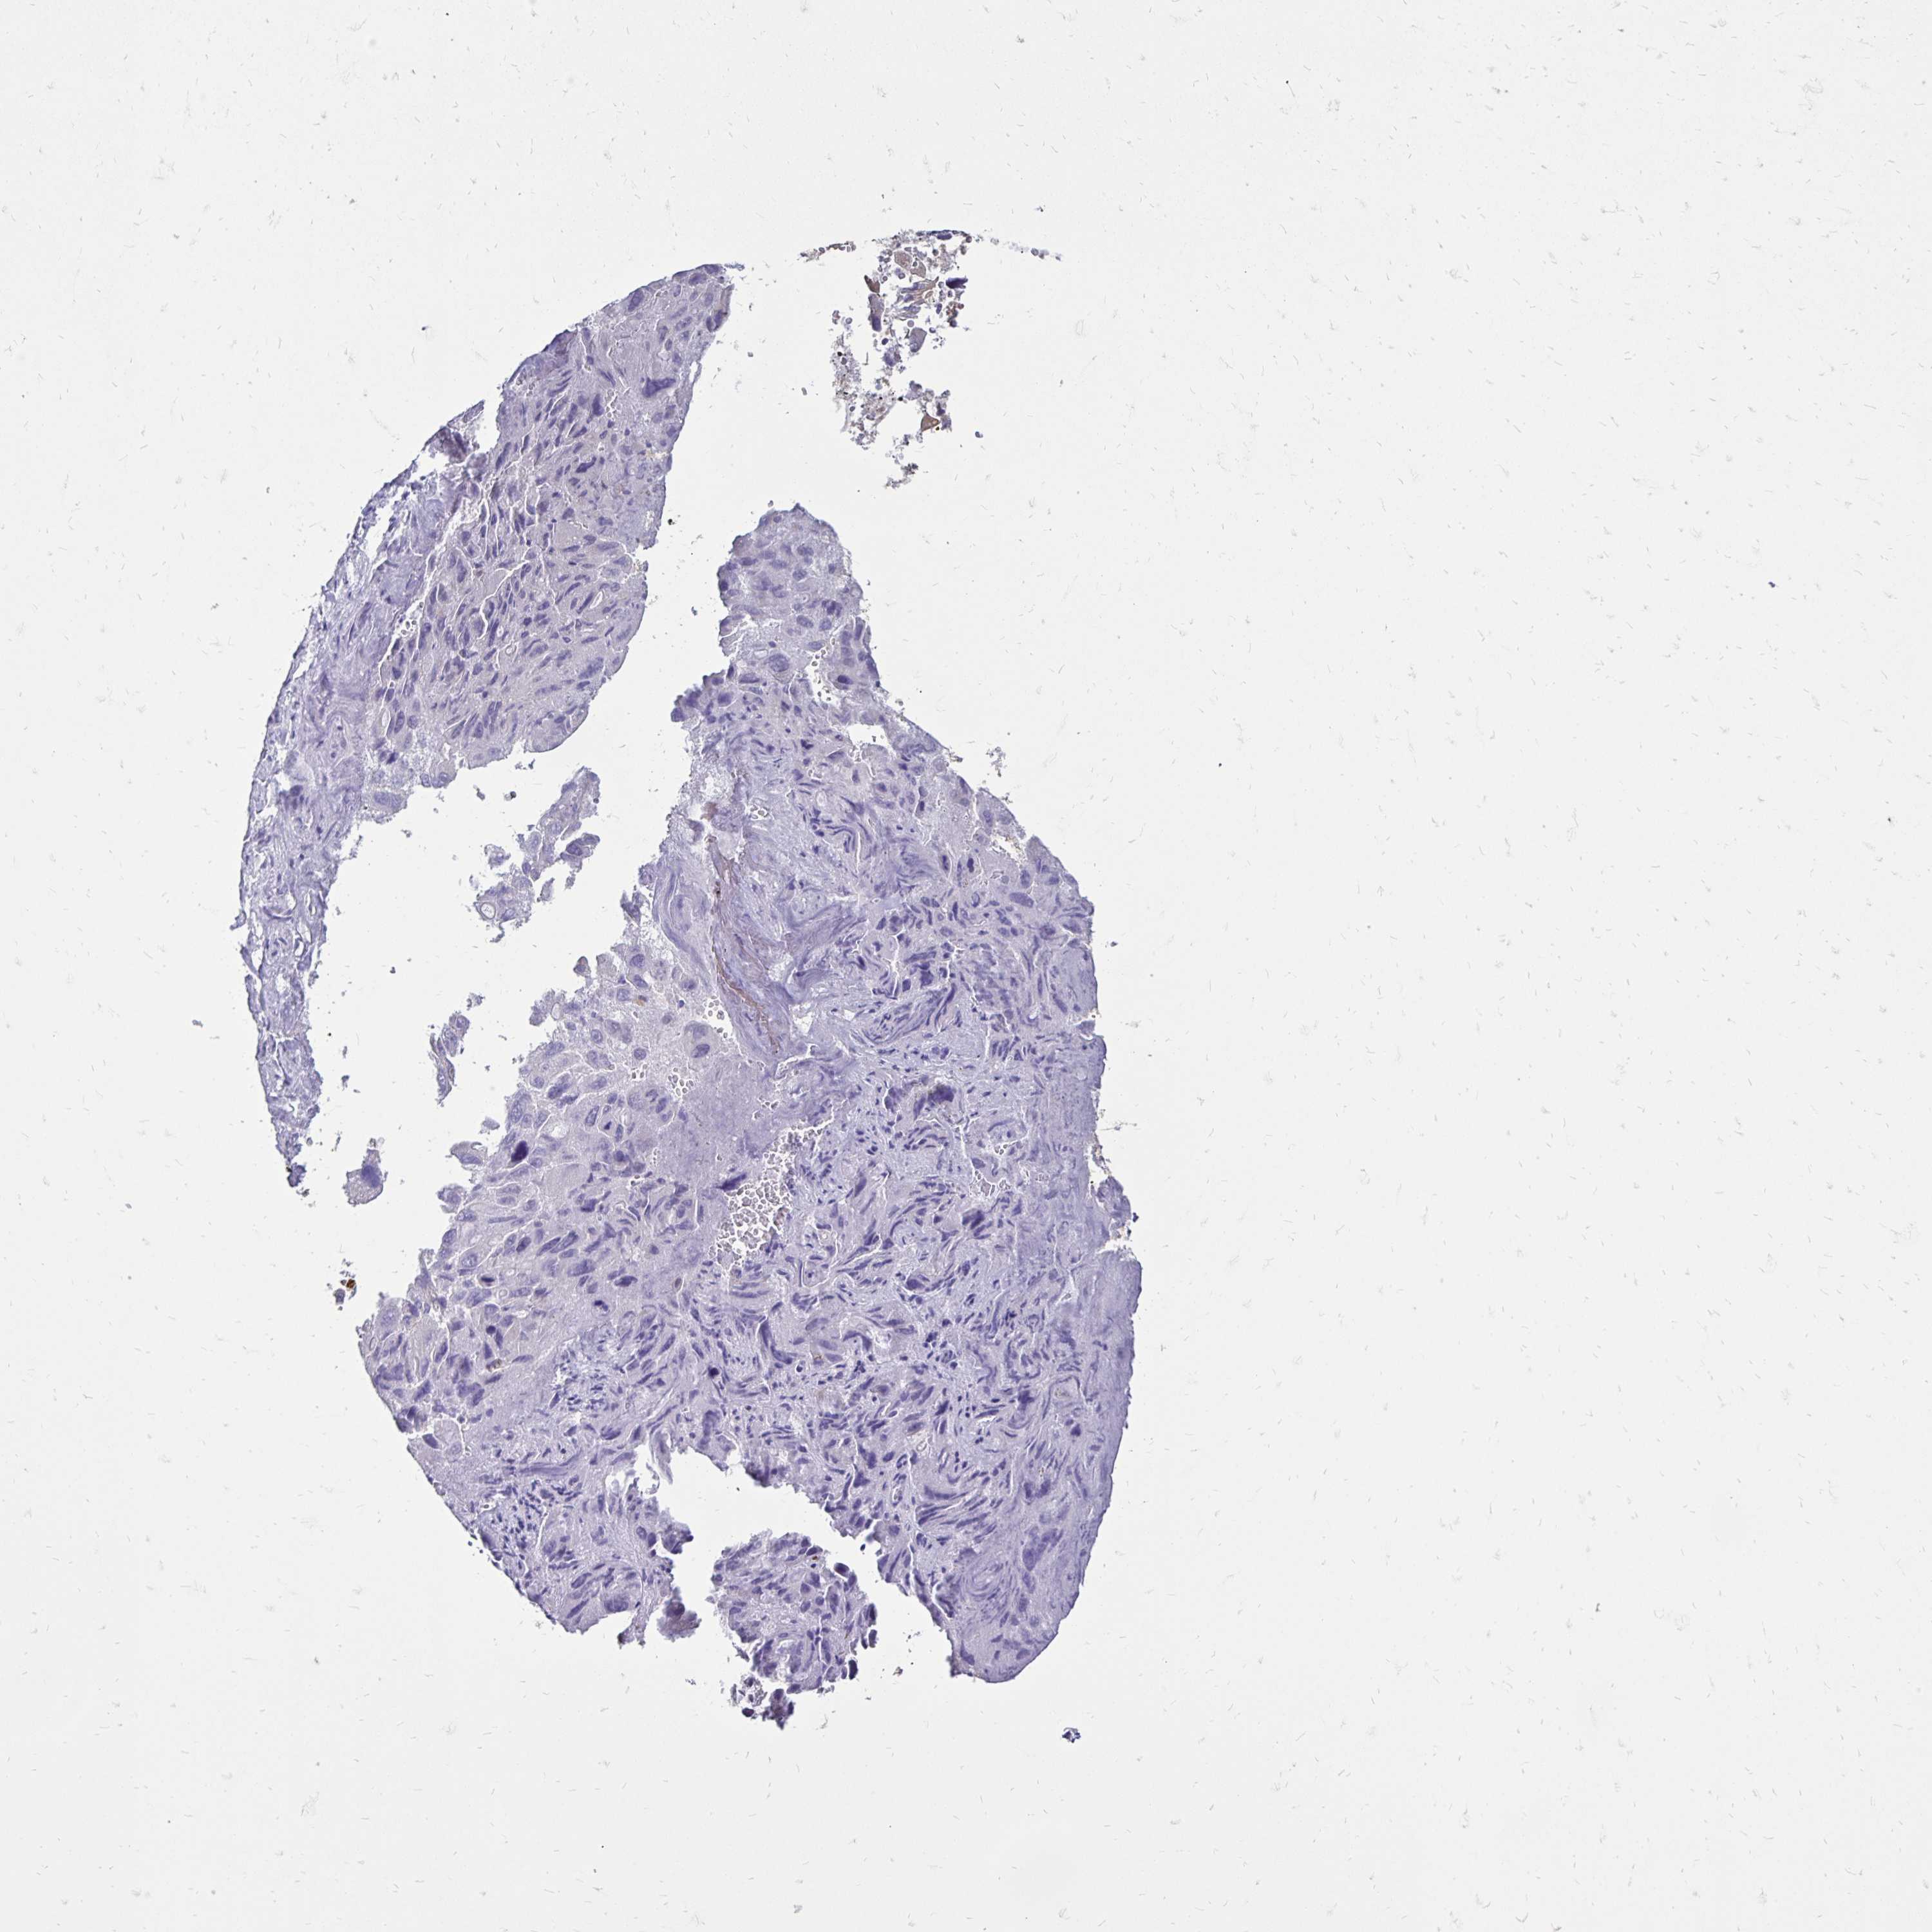

LIVER CANCER - Protein expressioni

A mouse-over function shows sample information and annotation data. Click on an image to view it in a full screen mode. Samples can be filtered based on level of antibody staining by selecting one or several of the following categories: high, medium, low and not detected. The assay and annotation is described here.

Note that samples used for immunohistochemistry by the Human Protein Atlas do not correspond to samples in the TCGA dataset.

Antibody stainingi

Antibody staining in the annotated cell types in the current human tissue is reported as not detected, low, medium, or high, based on conventional immunohistochemistry profiling in selected tissues. This score is based on the combination of the staining intensity and fraction of stained cells.

Each image is clickable and will lead to virtual microscopy that enables deeper exploration of all samples and also displays staining intensity scores, fraction scores and subcellular localization as well as patient and tissue information for each sample.

Antibody HPA053969

Antibody CAB002220

Carcinoma, Hepatocellular, NOS

Cholangiocarcinoma